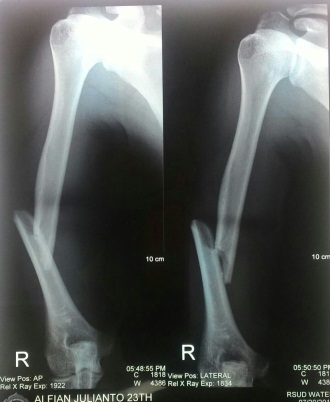

The shaft of a long bone is the center area, as in the middle of the bone, not at one of the ends. Diaphysis or shafts forms the long axis of the bone.

It was a little snapping noise and didnt hurt much. If the bone is broken, the doctor will probably call an orthopedist (a bone specialist) to put a cast on your child's fracture. The femur is the longest, largest, heaviest, and strongest bone in the body. When a bone is broken in more than two places or gets crushed, the name for it is a comminuted fracture. Still another condition is called a bowing still, broken bones should be treated quickly because they can restrict blood flow or cause nerve damage. All bone fractures, regardless of cause can be sorted into two major 2. The epiphysis and growth plates are found at the ends of the bones. There are different causes and types of fractures. A fracture in the shaft of a bone would be a break in the _. Shatters the bones into many small pieces. Transcript/notes how does a bone heal there are many different types of bone fractures, such as when a bone is shattered into multiple pieces, a linear fracture down the shaft, a displaced fracture where the bone is misaligned, or an. Most of us will break a bone at some point in our lives. Fractures can occur in any bone in the body. It makes standing and walking possible. Long bones are characterized by a bone shaft called a diaphysis. 16) the periosteum is secured to the underlying bone by dense connective tissue called _. Many scouting web questions are common questions that are typically seen.